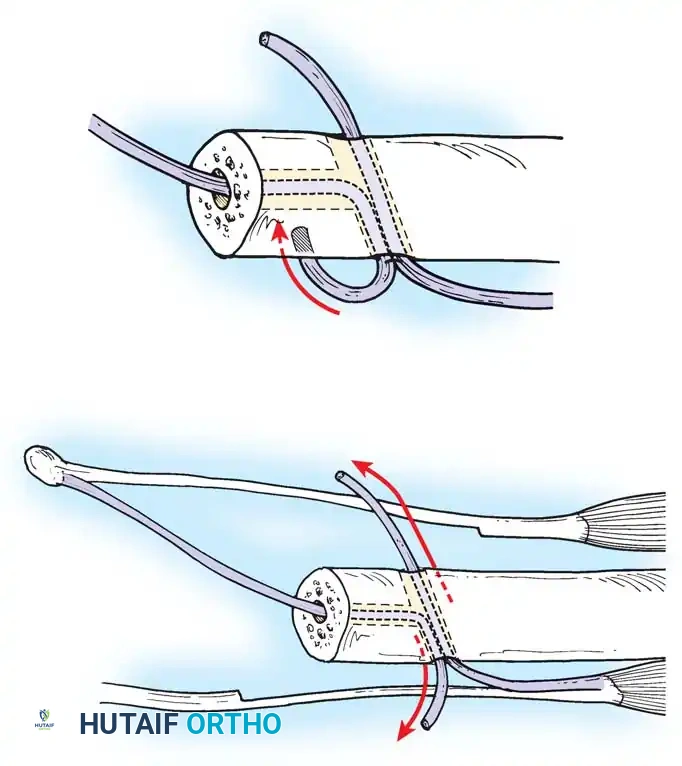

Passing non-absorbable sutures through the osseous tunnels in the ulna to capture the peripheral edge of the TFCC.

- Pass strong, non-absorbable sutures (e.g., 2-0 FiberWire) through the TFCC using an outside-in or inside-out technique, then shuttle the suture limbs down the osseous tunnels.

The sutures are tied securely over the cortical bone bridge of the ulnar neck, restoring tension to the radioulnar ligaments.

- Tie the sutures over the ulnar cortical bridge with the forearm in neutral rotation to restore anatomic tension.